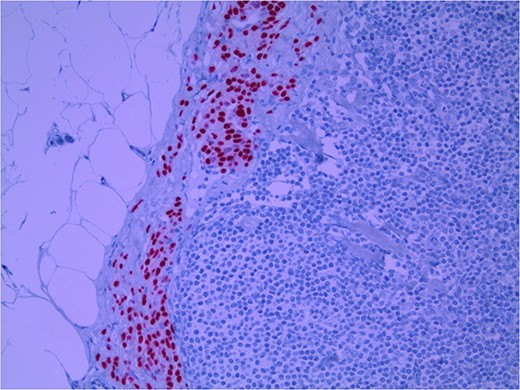

Lymph node specimens were sent for haematoxylin and eosin (H&E) staining (Fig. 3) and IHC analysis. The sections showed mild reactive changes and benign intracapsular nevoid rests. IHC analysis showed that these cells were negative for HMB-45 (Fig. 4) and were positive for both Sox10 and p16 (Figs 5 and 6). Consensus at the Multidisciplinary Team Meeting was that the appearance was in keeping with benign naevoid rests as opposed to melanoma deposits, given the location of the cells, morphology and immunohistochemistry. Surveillance was recommended.

Lymph node with IHC using p16 stain, staining nevoid melanocytes; × 100 magnification.

Several IHC stains are in use in the pathological interpretation of primary lesions and SLN biopsies. The antibody HMB-45 reacts with most melanomas. In a primary lesion, HMB-45 is immunoreactive with intraepidermal and superficial dermal components of benign nevi [14]. In a lymph node, however, benign nevoid cells are negative for HMB-45 and appear bland. A loss of HMB-45 expression has been reported in 20% of melanocytic metastasis, illustrating the need for further diagnostic testing [14]. Sox10 is a nuclear transcription factor that stains benign and malignant melanocytic cells. It indicates the extent of melanocytic spread but does not differentiate between benign nevi and metastatic melanoma [15]. Immunostaining for the tumour suppressor gene p16 differentiates between benign naevi and melanocytic metastases in the SLN. One study demonstrated positive nuclear and cytoplasmic p16 staining in all nevi (dermal and lymph node) and the absence of nuclear p16 staining in all but one melanoma metastasis [14]. No single stain is completely sensitive for melanocytic metastases, and a confident diagnosis relies upon cell location, morphology and multiple IHC techniques. SLN biopsy in the current patient demonstrated intracapsular melanocytic cells which stained negative for HMB-45, and positive for Sox10 and p16, in keeping with benign nevoid rests as opposed to metastatic melanoma.